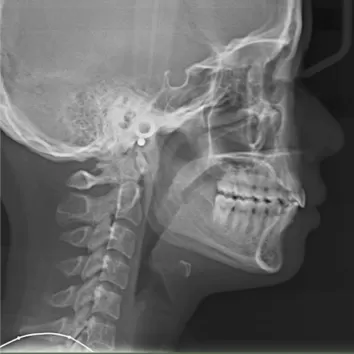

Female, 25 years old. Chief complaint: protruding and misaligned teeth, requiring orthodontic treatment.

X-rays before treatment

[Panoramic Radiography/Lateral Cephalogram]